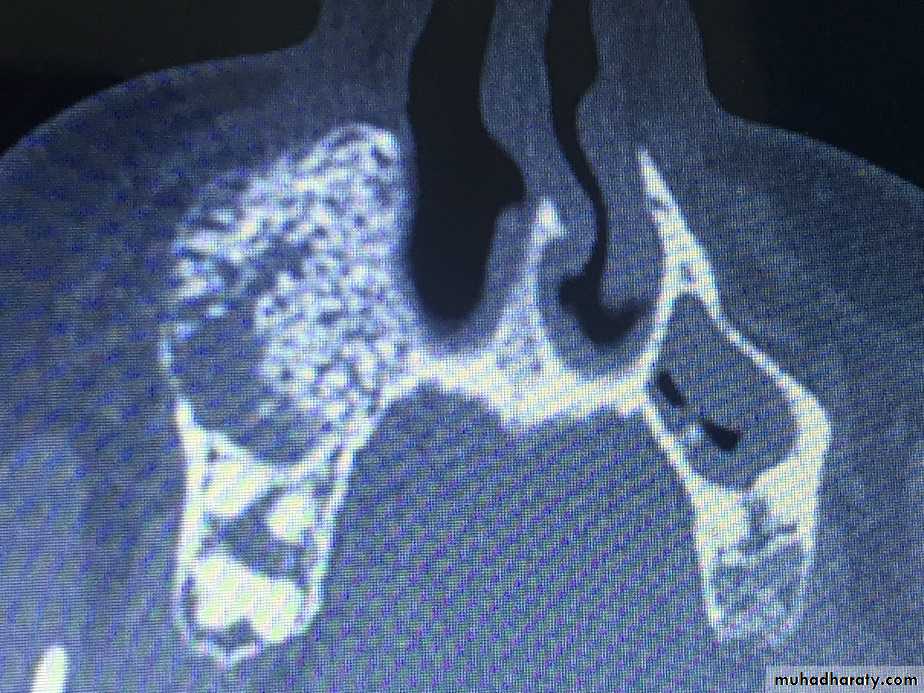

These tumors of embryonic tissue origin developing from immature primitive bone or cartilage cells. the myxoma may simulate a cystic lesion because of its honeycomb appearance in the x-rays, Expansion of the bone cortex occurs with the appearance of mucoid material replacing bone architecture.The chondroma arises from aberrant fetal cartilage in specific regions of the mandible such as the symphysis and coronid and condyloid process. Myxoma and chondroma may be detected clinically by pain swelling and limitation of motion. these tumors grow slowly they are extripated surgically.